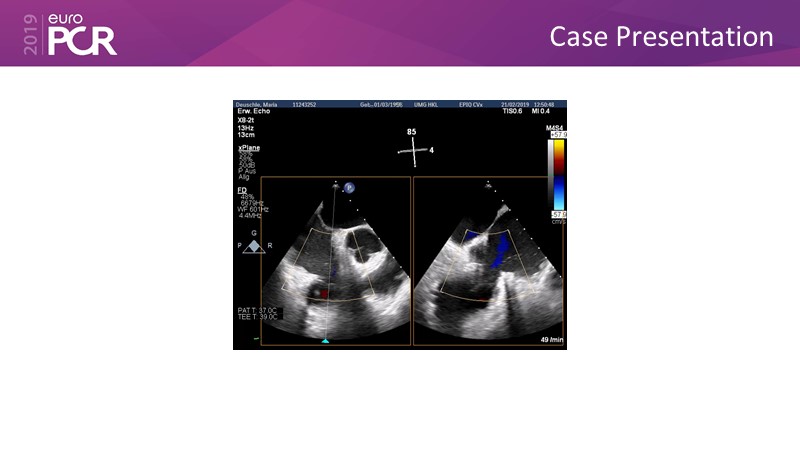

Addressing tricuspid regurgitation with annular reduction: the Cardioband tricuspid system

Consult this session to understand how patients with tricuspid regurgitation and annular dilatation can benefit from Cardioband system...

- To understand how patients with tricuspid regurgitation and annular dilatation can benefit from Cardioband system

- To learn how to perform a good echo workup for Cardioband tricuspid system